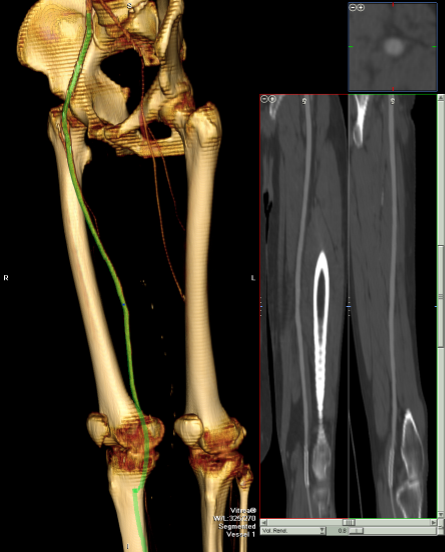

PVR’s demonstrate the presence of severe inflow (aortoiliac occlusive disease or AIOD). CTA was acquired and the findings were consistent with the PVR’s.

There was diffuse bilateral iliac atherosclerotic plaque with occlusion of the right common femoral artery and left common and external iliac artery. The 3DVR (three dimensional virtual reality) reconstruction image below shows this as well as the abdominal and pelvic wall collaterals feeding the legs around the occluded iliofemoral system.

The postoperative CTA shows good results as well. Below is the composite right and left centerline from aorta to the PFA’s.

The 3DVR reconstruction images are shown below, with the comparison to preop shown in the first image of this blog entry:

The pre and postoperative images of the centerlines (composited) are shown below: